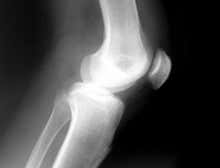

Artificial cartilage could outperform the real thing